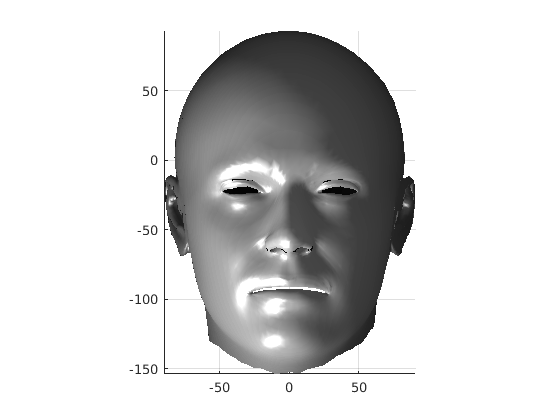

Following this, OSNR ICP iterates over a set of decreasing mesh stiffnesses (typically 10), until the registration between the template and the scan is below some error or a maximum number of iterations is reached. Figure 28 shows a selection of template warp results. The template appears to be accurately warped onto the scan, at least in the normal direction of the surfaces, it is not possible to see error tangential to the surface. Furthermore, we have noted errors on some scans on the ears. To improve these we need a method of automatically landmarking the ears, which is an area for further work.

|

|

|

|

|

|

|

|

The first two modes of head variation are shown in figures 29 and 30. These include the cranial height / facial angle mode and the (almost) pure size mode, as seen in the sagittal profile model.